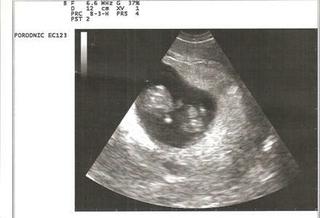

Ja som dnes bola na kontrole a vsetko je v o.k. sedime presne na tt a lieky mam dobrat. Babo sa ma fajn kopkalo nozickami a aj kyvalo rucickami, ale ked ho dr. chcela odfotit tak sa rychlo skrylo. Tak ho tam dr. nahanala a vravela ,ze doma chcu vidiet aj nohy 🙂b no ale nakoniec sa jej podarilo ho aj odfotit.